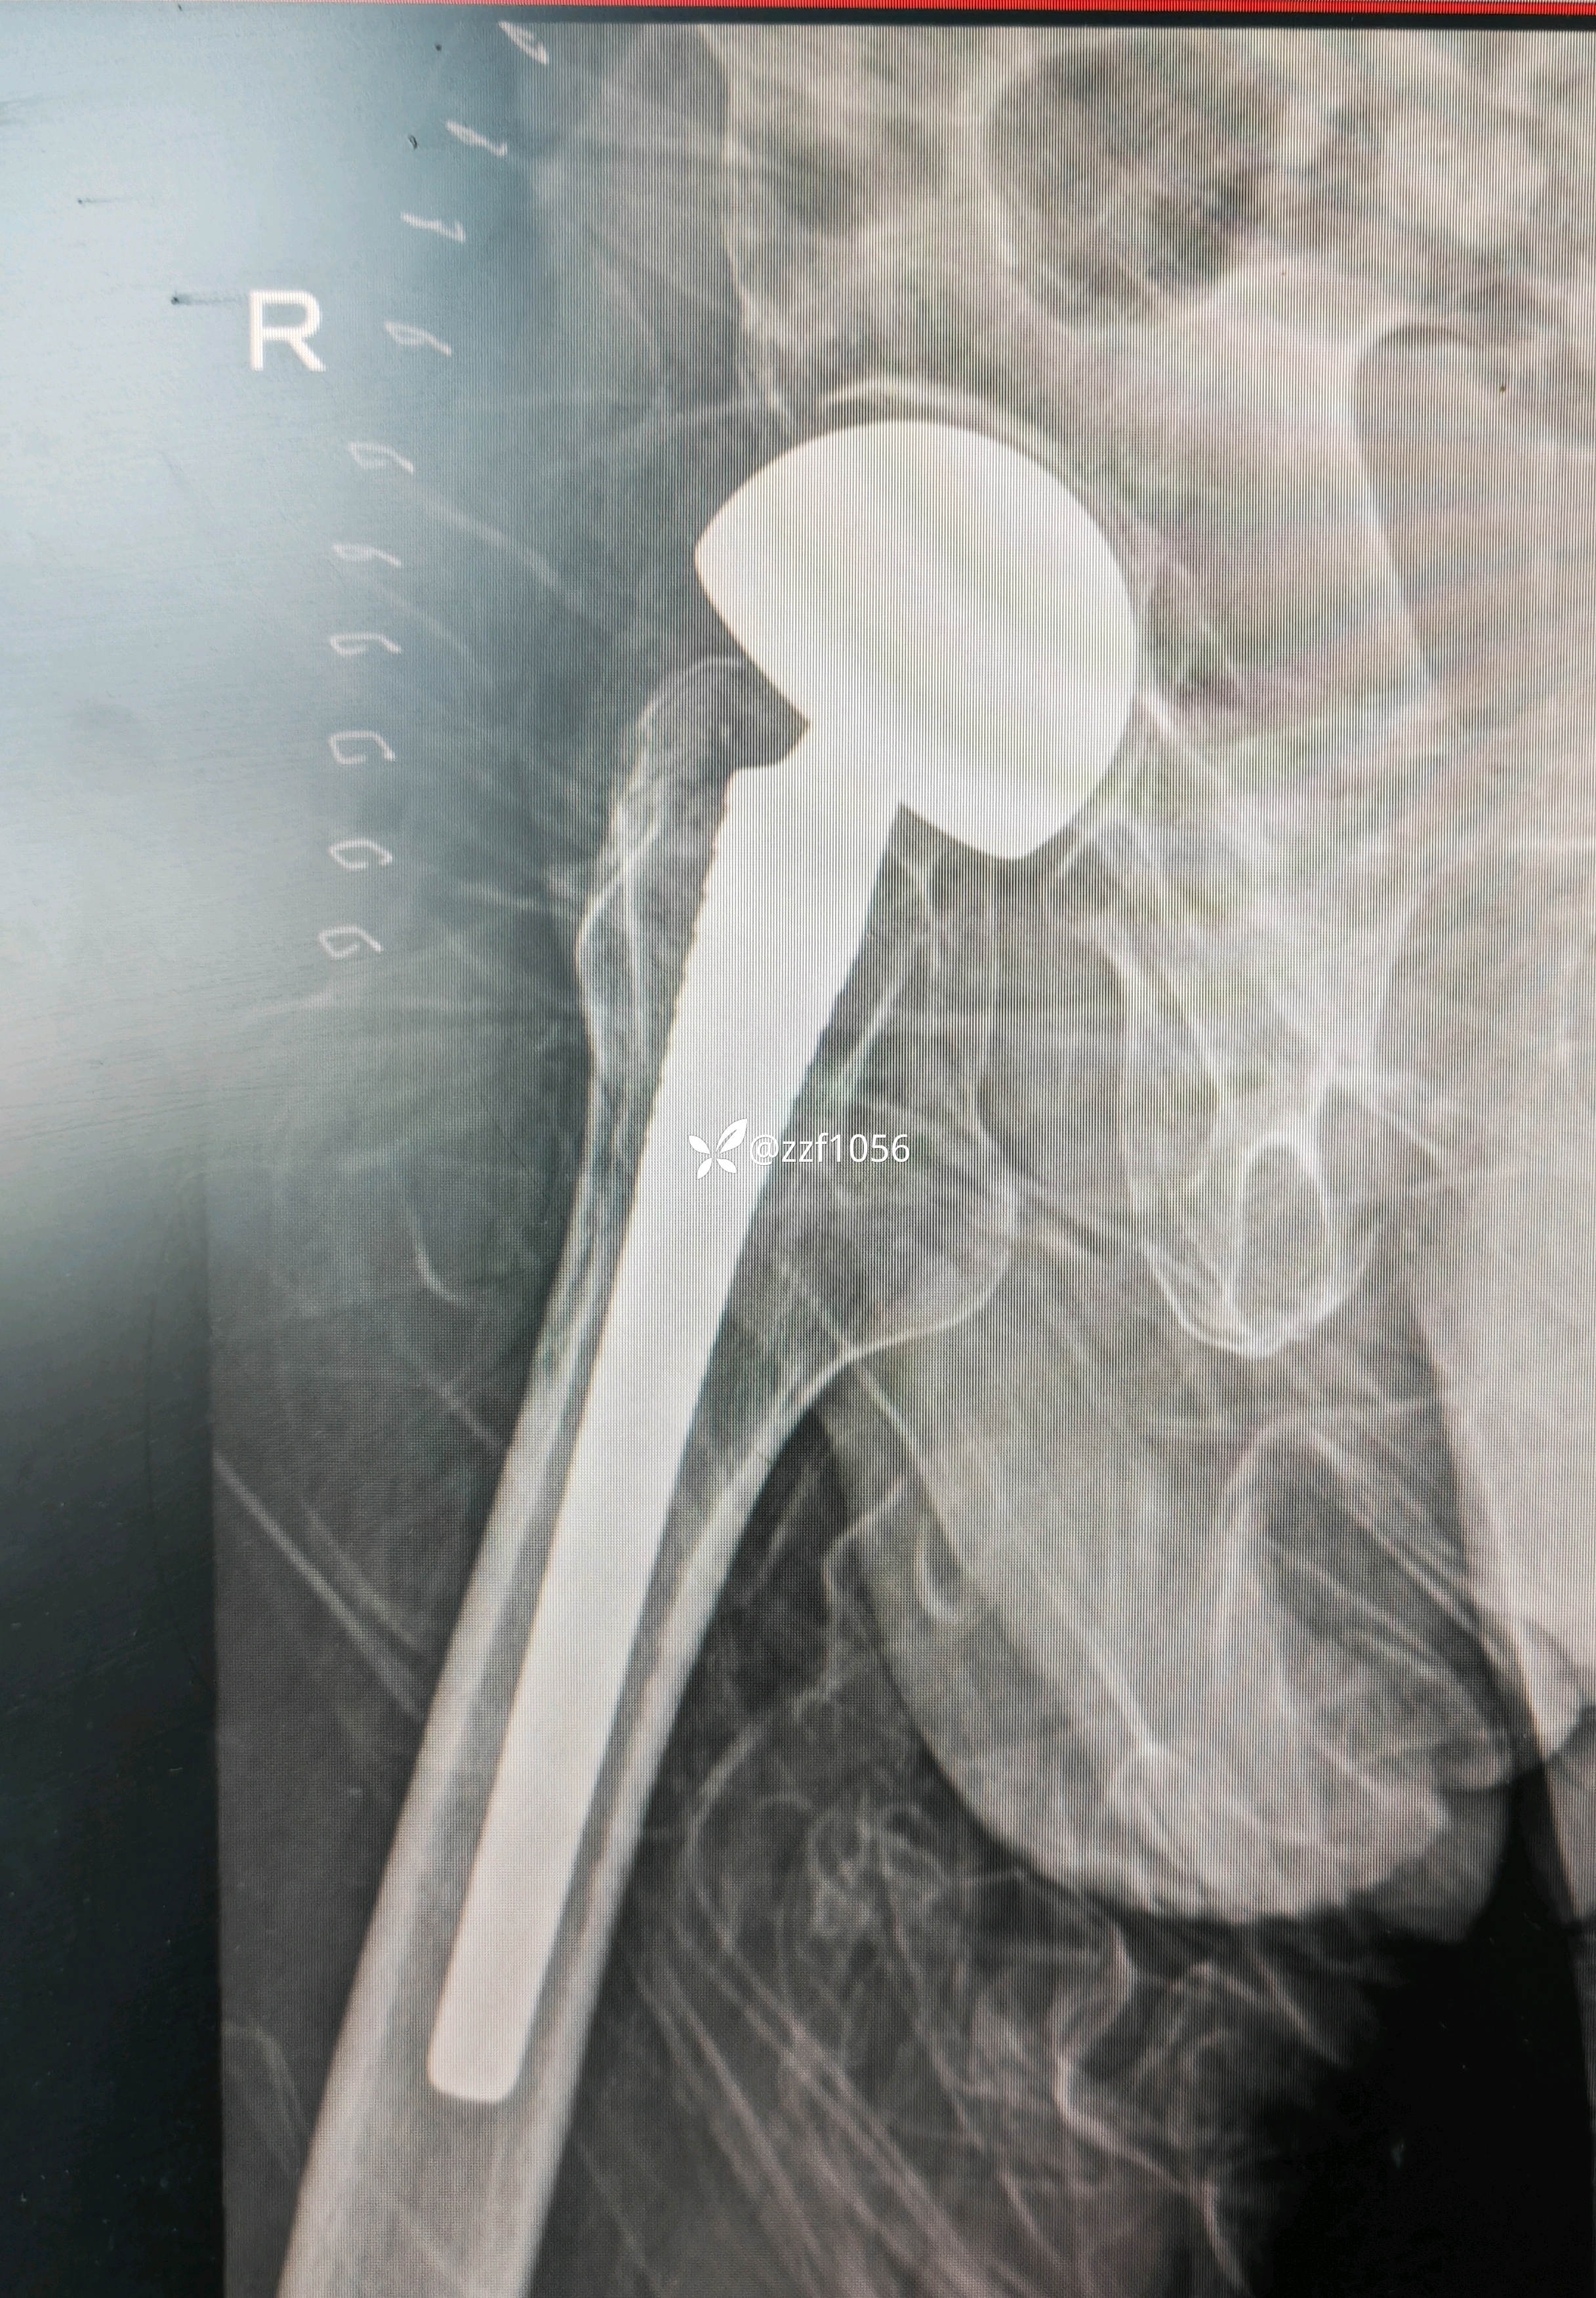

顺利实施手术双动头置换

术后下床行走恢复良好,今日拆线出院。